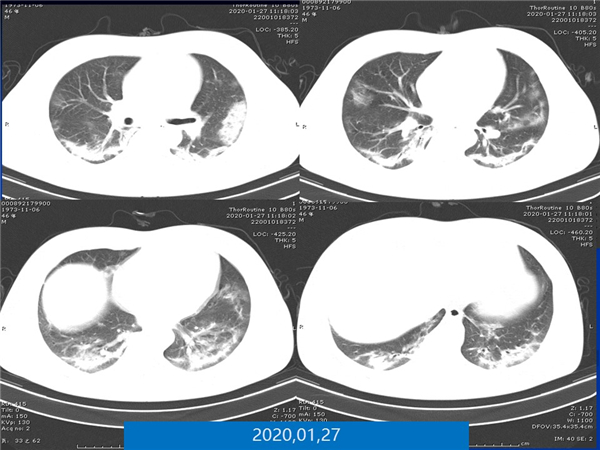

【病例分享】新型冠狀病毒感染肺部CT影像4例(常德市第一人民醫(yī)院)

幻燈片7.jpg